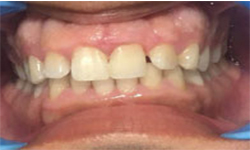

(7) Clinical Case-Veneer

Before Treatment

After Treatment

This female patient, with age 28 yrs came with a complaint of dirty teeth and an unaesthetic tooth in upper front left side of mouth. The patient has been treated with a thorough oral prophylaxis followed by veneering of the tooth.